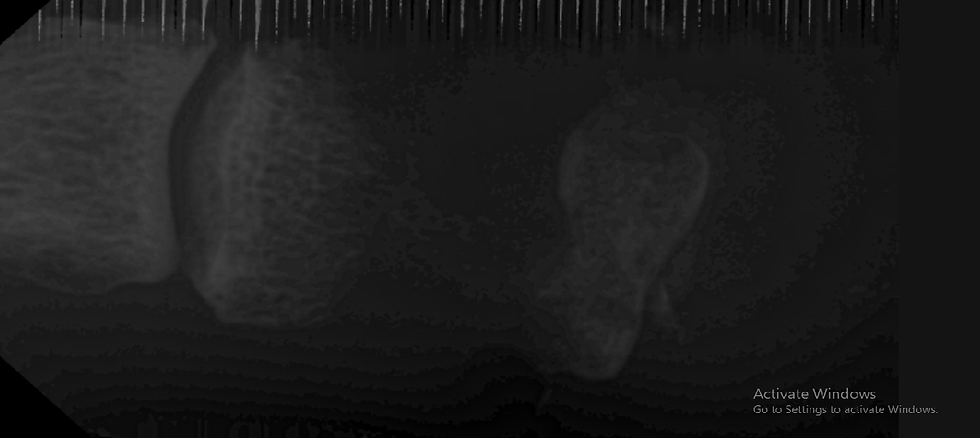

X-ray of the toe suggests osteomyelitis of the 2nd phalanx.

Image 3. X ray Lat. View of 2nd toe of same patient showing osteomylitis.

Image 4 X ray AP view of 2nd toe of same patient.